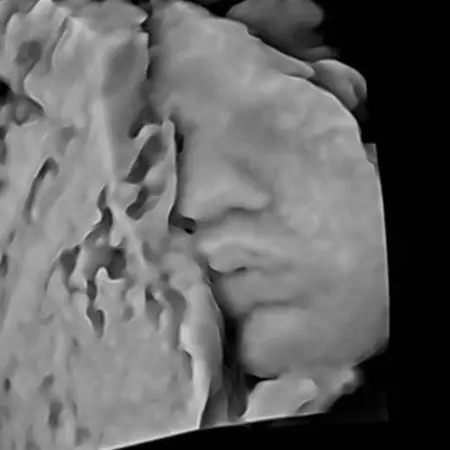

Image

Α' τρίμηνο